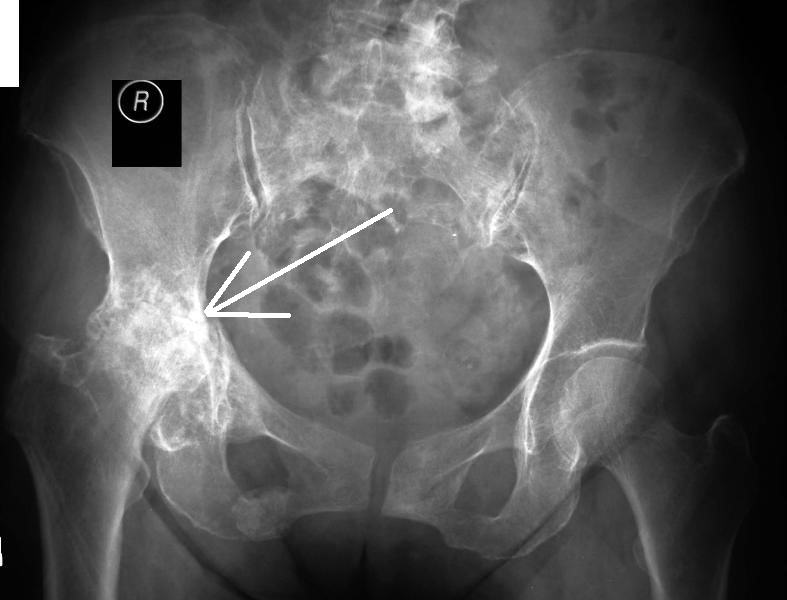

Для более точной оценки состояния суставов назначается рентгенография. Это исследование позволяет обнаружить увеличение головки бедренной кости, признаки деформации, сужение суставных щелей и наличие костных наростов. В некоторых случаях для детального изучения изменений и определения стадии заболевания могут быть рекомендованы компьютерная томография (КТ) или магнитно-резонансная томография (МРТ). Также может быть назначено ультразвуковое исследование и другие диагностические процедуры.